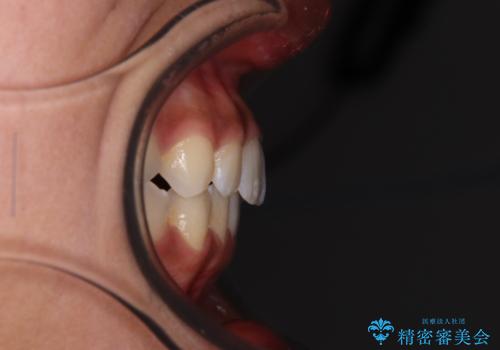

- 上下前歯の叢生を気にして来院された患者様です。

インビザラインでの治療を希望されていて、デコボコの程度が中等度であり、安価なパッケージにて対応可能と判断されたため、インビザライン・モデレートを用いて矯正治療を行うこととしました。